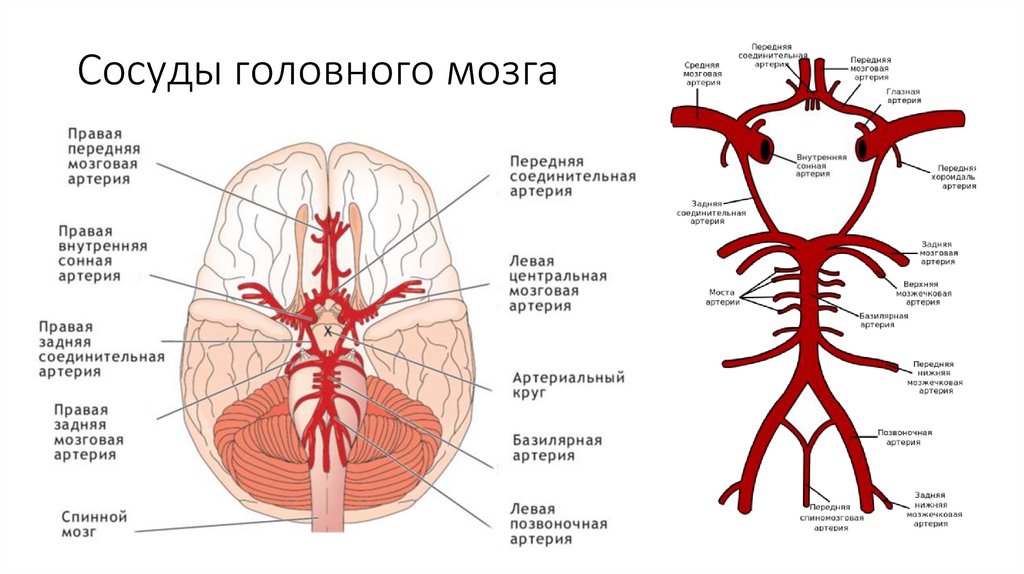

Анатомия: Задняя соединительная артерия мозга

:max_bytes(150000):strip_icc()/CircleofWillis-87378170-3ece0502a02949dd82310d723e0d4c98.jpg)

Раздел: Фотоэссе